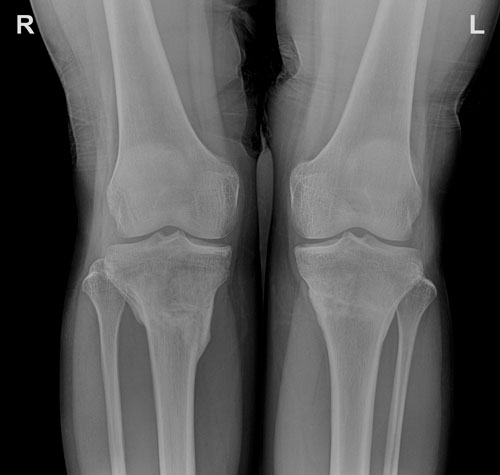

Рентген в 90 дней перед снятием аппаратов!

Вот и настал тот долгожданный и трепетный момент. Сделала рентген в 90 дней. Осмотрев снимок Николай Николаевич, сказал, что уже можно снимать аппараты. В тот день он ослабил болтики, а сняли аппараты на следующий. Перед снятием аппаратов не принимала никаких обезболивающих средств. Я была готова на худшее. Но это действительно было не так страшно. Скорее больше страха в ожидании боли. Да и что скрывать, мой болевой порог высокий. Не знаю это плюс или минус... Происходило это следующим образом: сначала раскрутили болтики, дальше было обкусывание спиц и в конце их вытаскивание. Последние два этапа смотреть я не стала. Было немножко неприятно. Вся процедура заняла максимум 5-8 минут. Так что, по моему мнению, это короткая и вполне терпимая боль. Думаю, что столько перенесли после операции (заново учиться делать свои первые шаги, ходить, крутки, ротация и т.д.), то можно с достоинством, стиснув зубы, потерпеть завершающий этап на пути к красивым ножкам .

Вот и финиш. Ножки получились красивыми, стройными. Коленки в первый раз в жизни соединяются легко, чего до операции не было, даже если напрягалась, чтобы соединить их. Через определенное время ножки придут в тонус, потом нужно будет накачать икры.